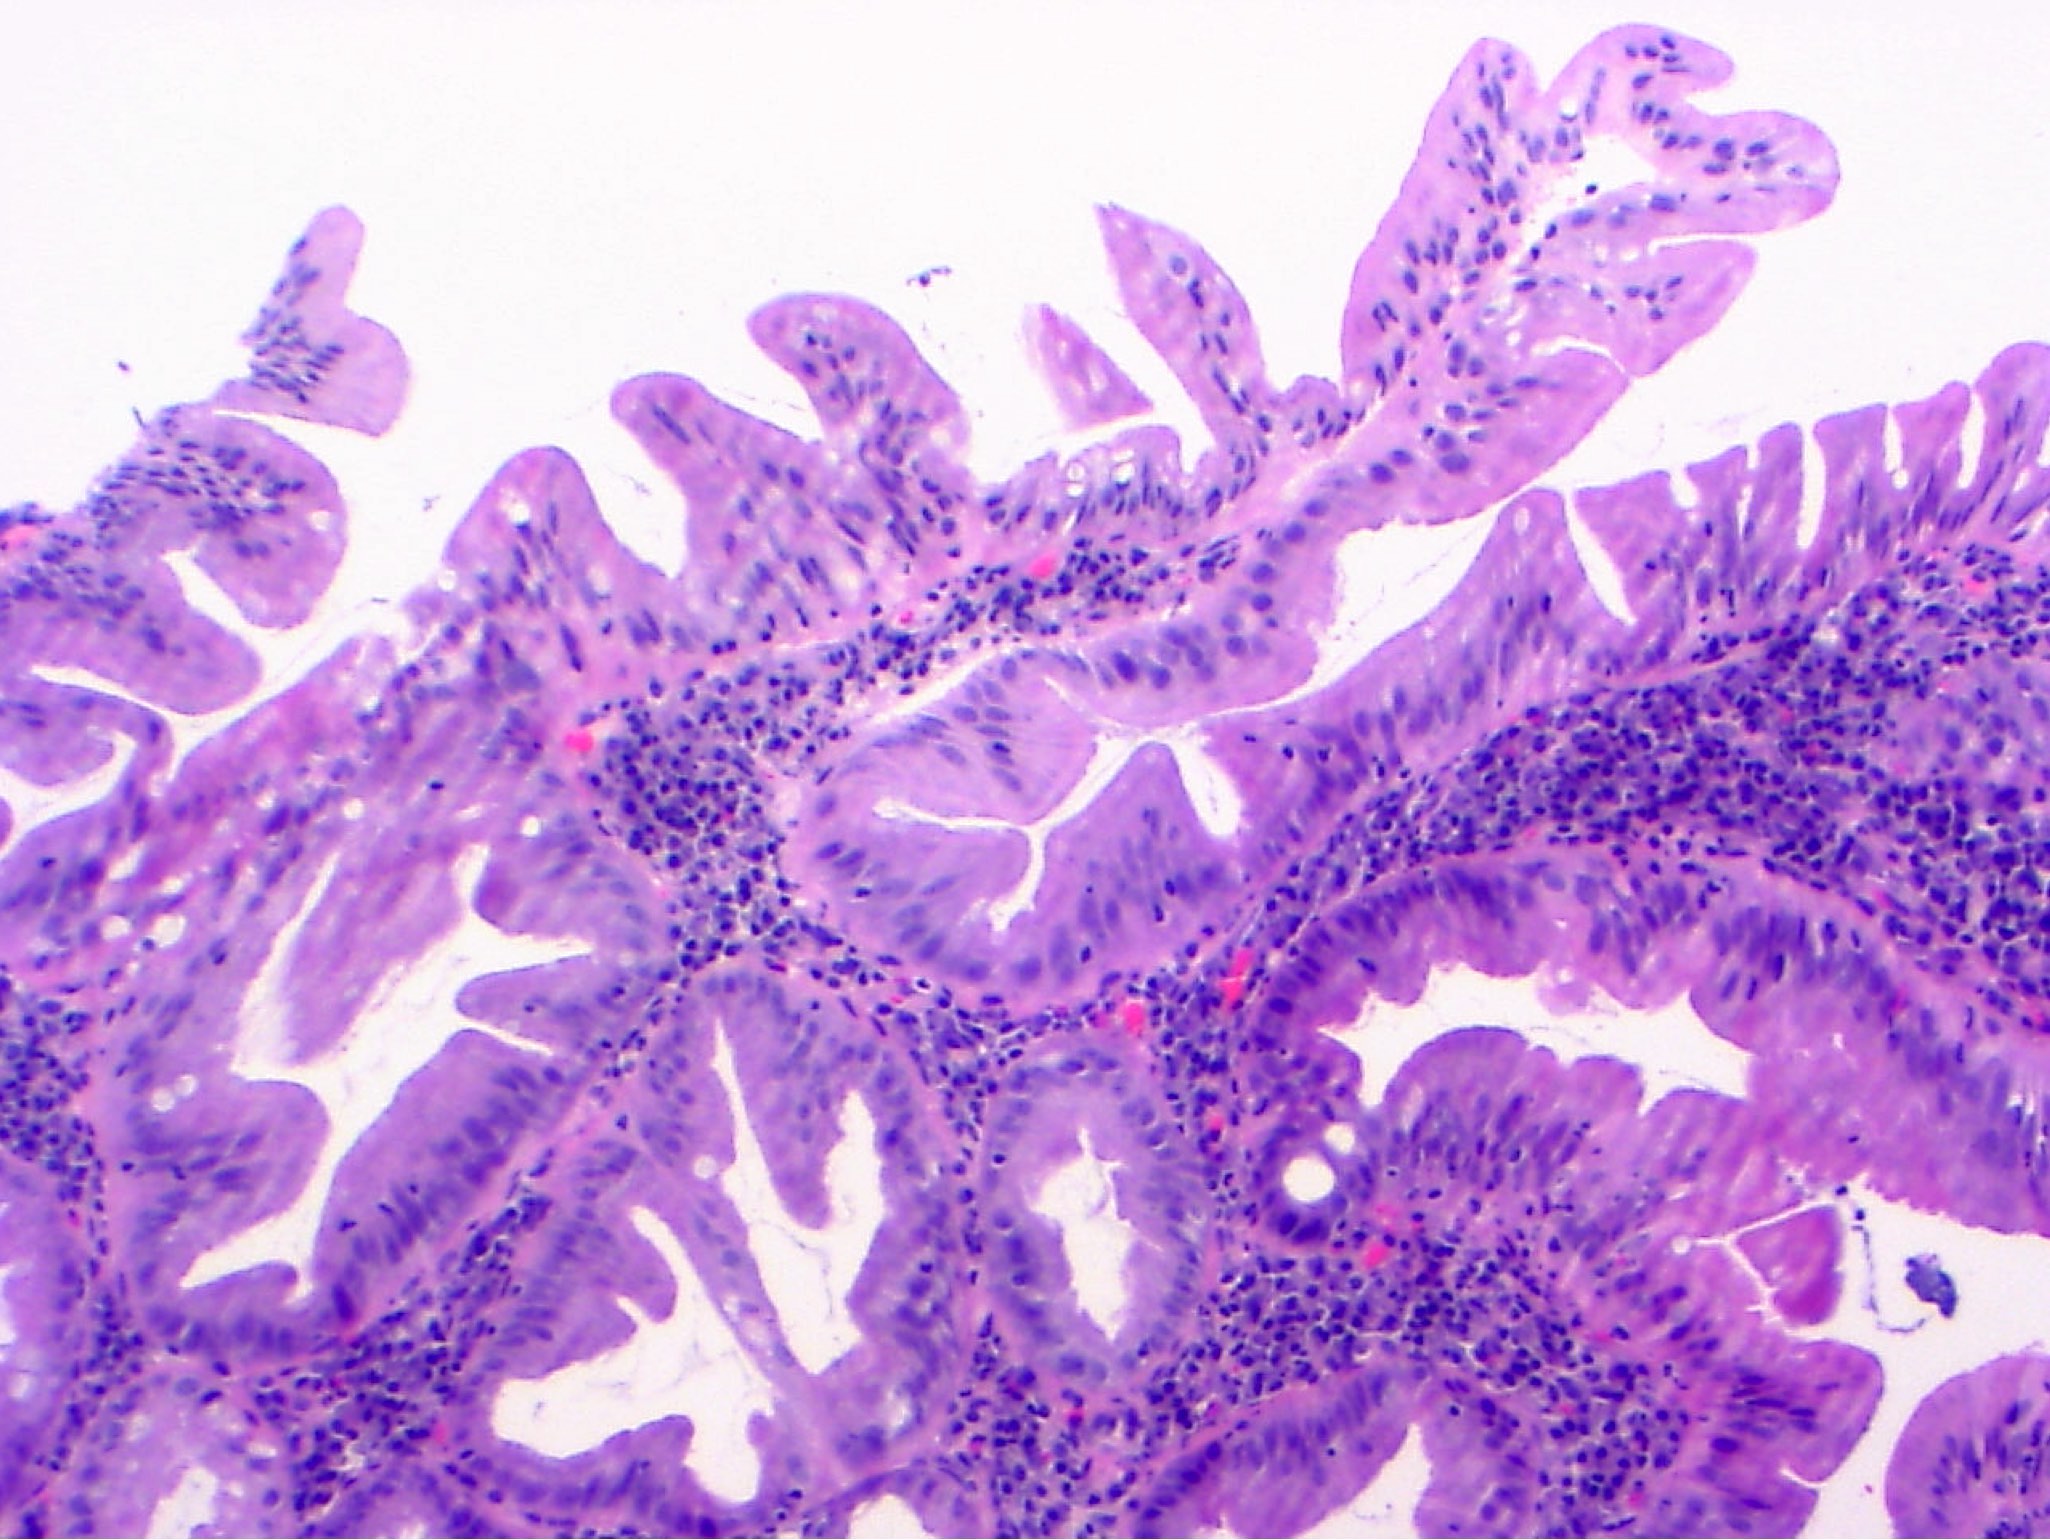

Microscopic (histologic) description

- Low grade dysplasia:

- Preserved nuclear polarity

- Pseudostratified, crowded, elongated and hyperchromatic nuclei

- Lack of surface maturation, i.e. abnormalities persist to surface

- IBD associated nonconventional dysplasia (i.e. not intestinal type) has been described and is relatively common in IBD patients:

- Nonconventional dysplasia subtypes (Histopathology 2021;78:814, Hum Pathol 2020;100:24, Mod Pathol 2020;33:933):

- Hypermucinous (mucinous) dysplasia:

- Tubulovillous or villous architecture with prominent mucinous differentiation

- Usually mild nuclear atypia, especially towards the surface

Microscopic (histologic) images